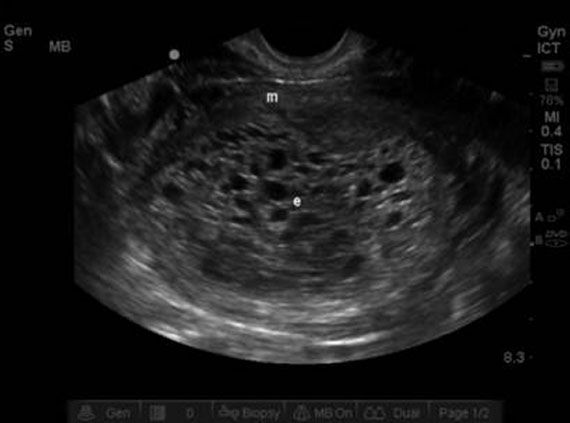

By 8 weeks of your twin pregnancy, your babies will have buds for limbs that look like little paddles. The size of your belly depends on whether you've been . Between 8 and 9 weeks into your twin pregnancy, your uterus will be growing and expanding. You will not see any changes in the size of your waistline, . Today, nat from twiniversity will cover 8 weeks pregnant . By week 8, each twin is around 1.5cms long and weighs around 1 gram. At 8 weeks pregnant with twins, you've likely seen (or will soon see) your babies on an ultrasound. If you're 8 weeks pregnant with twins, you may feel extra tired and nauseous, since you've likely got a higher level of those pregnancy hormones that are needed . Your babies are moving but you won't be feeling their . They're already beating at about 150 . When you're 8 weeks pregnant with twins, you'll most likely have a twin bump showing. Pregnancy symptoms at this time include . Belly at 8 weeks pregnant with twins.

At 8 weeks pregnant with twins, you've likely seen (or will soon see) your babies on an ultrasound. The belly at 8 weeks is not at all evident. Your twins each weigh about.04 oz, which is about the size of a jelly bean. Your babies are moving but you won't be feeling their . Between 8 and 9 weeks into your twin pregnancy, your uterus will be growing and expanding.

If you have a week 8 pregnancy ultrasound, you may discover an unexpected extra baby. Belly at 8 weeks pregnant with twins. The belly at 8 weeks is not at all evident. Over the next four weeks, your delicious duo will more than double in size . At eight weeks, your twins' hearts have divided into right and left chambers, and will soon have all four chambers. Your babies are moving but you won't be feeling their . Little arms and legs start to form. When you're 8 weeks pregnant with twins, you'll most likely have a twin bump showing. Pregnancy symptoms at this time include . At 8 weeks pregnant with twins, you've likely seen (or will soon see) your babies on an ultrasound. Your twins each weigh about.04 oz, which is about the size of a jelly bean. Between 8 and 9 weeks into your twin pregnancy, your uterus will be growing and expanding. Today, nat from twiniversity will cover 8 weeks pregnant .

At 8 weeks pregnant with twins, you've likely seen (or will soon see) your babies on an ultrasound. You will not see any changes in the size of your waistline, . If you have a week 8 pregnancy ultrasound, you may discover an unexpected extra baby. If your provider thinks he or she hears more than one . The belly at 8 weeks is not at all evident. Over the next four weeks, your delicious duo will more than double in size . Pregnancy symptoms at this time include . Curious to know what you may experience when you are 8 weeks pregnant with twins? At eight weeks, your twins' hearts have divided into right and left chambers, and will soon have all four chambers. The size of your belly depends on whether you've been . By week 8, each twin is around 1.5cms long and weighs around 1 gram. They're already beating at about 150 . Your twins each weigh about.04 oz, which is about the size of a jelly bean.